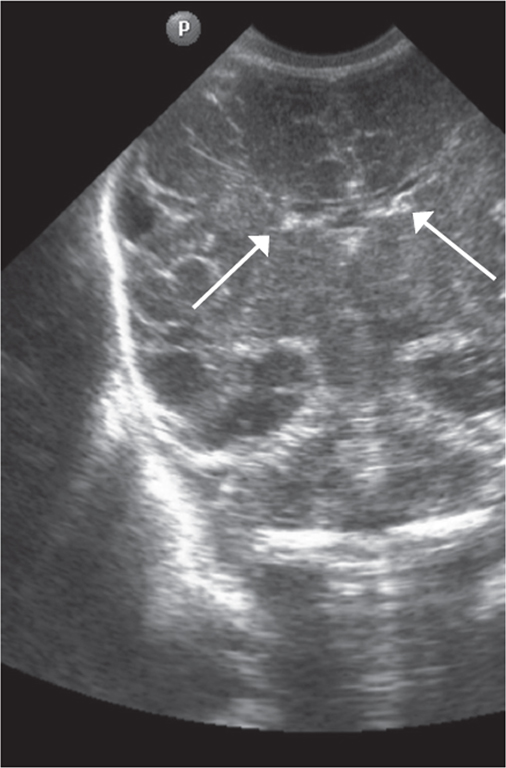

Краниальная сонография выполнена всем новорожденным (4 недоношенным новорожденным 25 недель гестации, 5 недоношенным 26 недель гестации, 3 недоношенным новорожденным 27, 28, 29 недель гестации) по общепринятой методике через большой родничок с использованием микроконвексного и линейного датчиков (5–7 Гц), аппарат Philips HD11 [14]. Методом КСГ проведено измерение визуализируемого гериминального матрикса в передних отделах боковых желудочков (проекция отверстия Монро), определяли толщину герминального матрикса, единицы измерения представлены в миллиметрах (мм) системы СИ (рис. 1).

Рис. 1. Краниальная сонография недоношенного новорожденного, 28 недель гестации, фронтальный скан. Стрелками указаны области визуализации герминального матрикса

Fig. 1. CUS image of preterm newborn, gestational age 28 wks., frontal scan. Arrows indicate the area of visualization of the germinal matrix